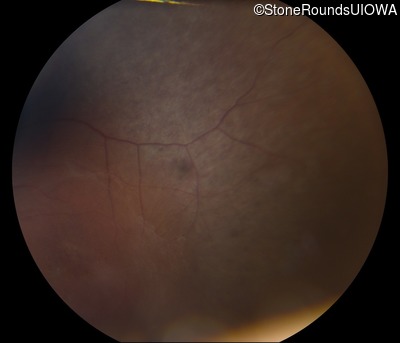

Fundus Photography - Left - Count Fingers 6"

Exemplar